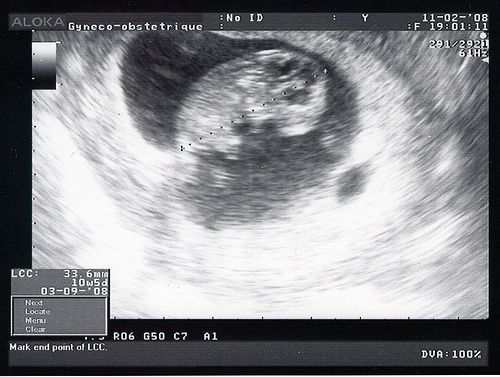

ou 10 sa et 5 jours...

Qu'est ce que tu as grandi! Tu vas bien, ton coeur bat, je l'ai vu, je l'ai entendu. Je t'ai vu bouger et je ne stresse plus. Tu mesures 3,6 cm! On voit bien ton profil, ton coeur en plus foncé sous le menton. Le gynéco a mesuré ta nuque et elle est toute fine, ça limite grandement le risque pour le syndrome de Down. C'est la trisomie, une maladie génétique. Je devrai faire d'autres tests dans une prise de sang pour m'assurer que tu n'auras pas cette maladie très grave qui déforme le corps, le visage et qui rend plus lent (un handicap mental brrr). Je suis déjà rassurée par la taille de la nuque. Ces risques augmentent en fonction de l'âge de la mère et des conditions de grossesse. Mais je suis jeune (28 ans, ça va non?), je ne bois pas, je ne fume pas, je ne me drogue pas. Je reste confiante. Je ferai la prise de sang assez vite.